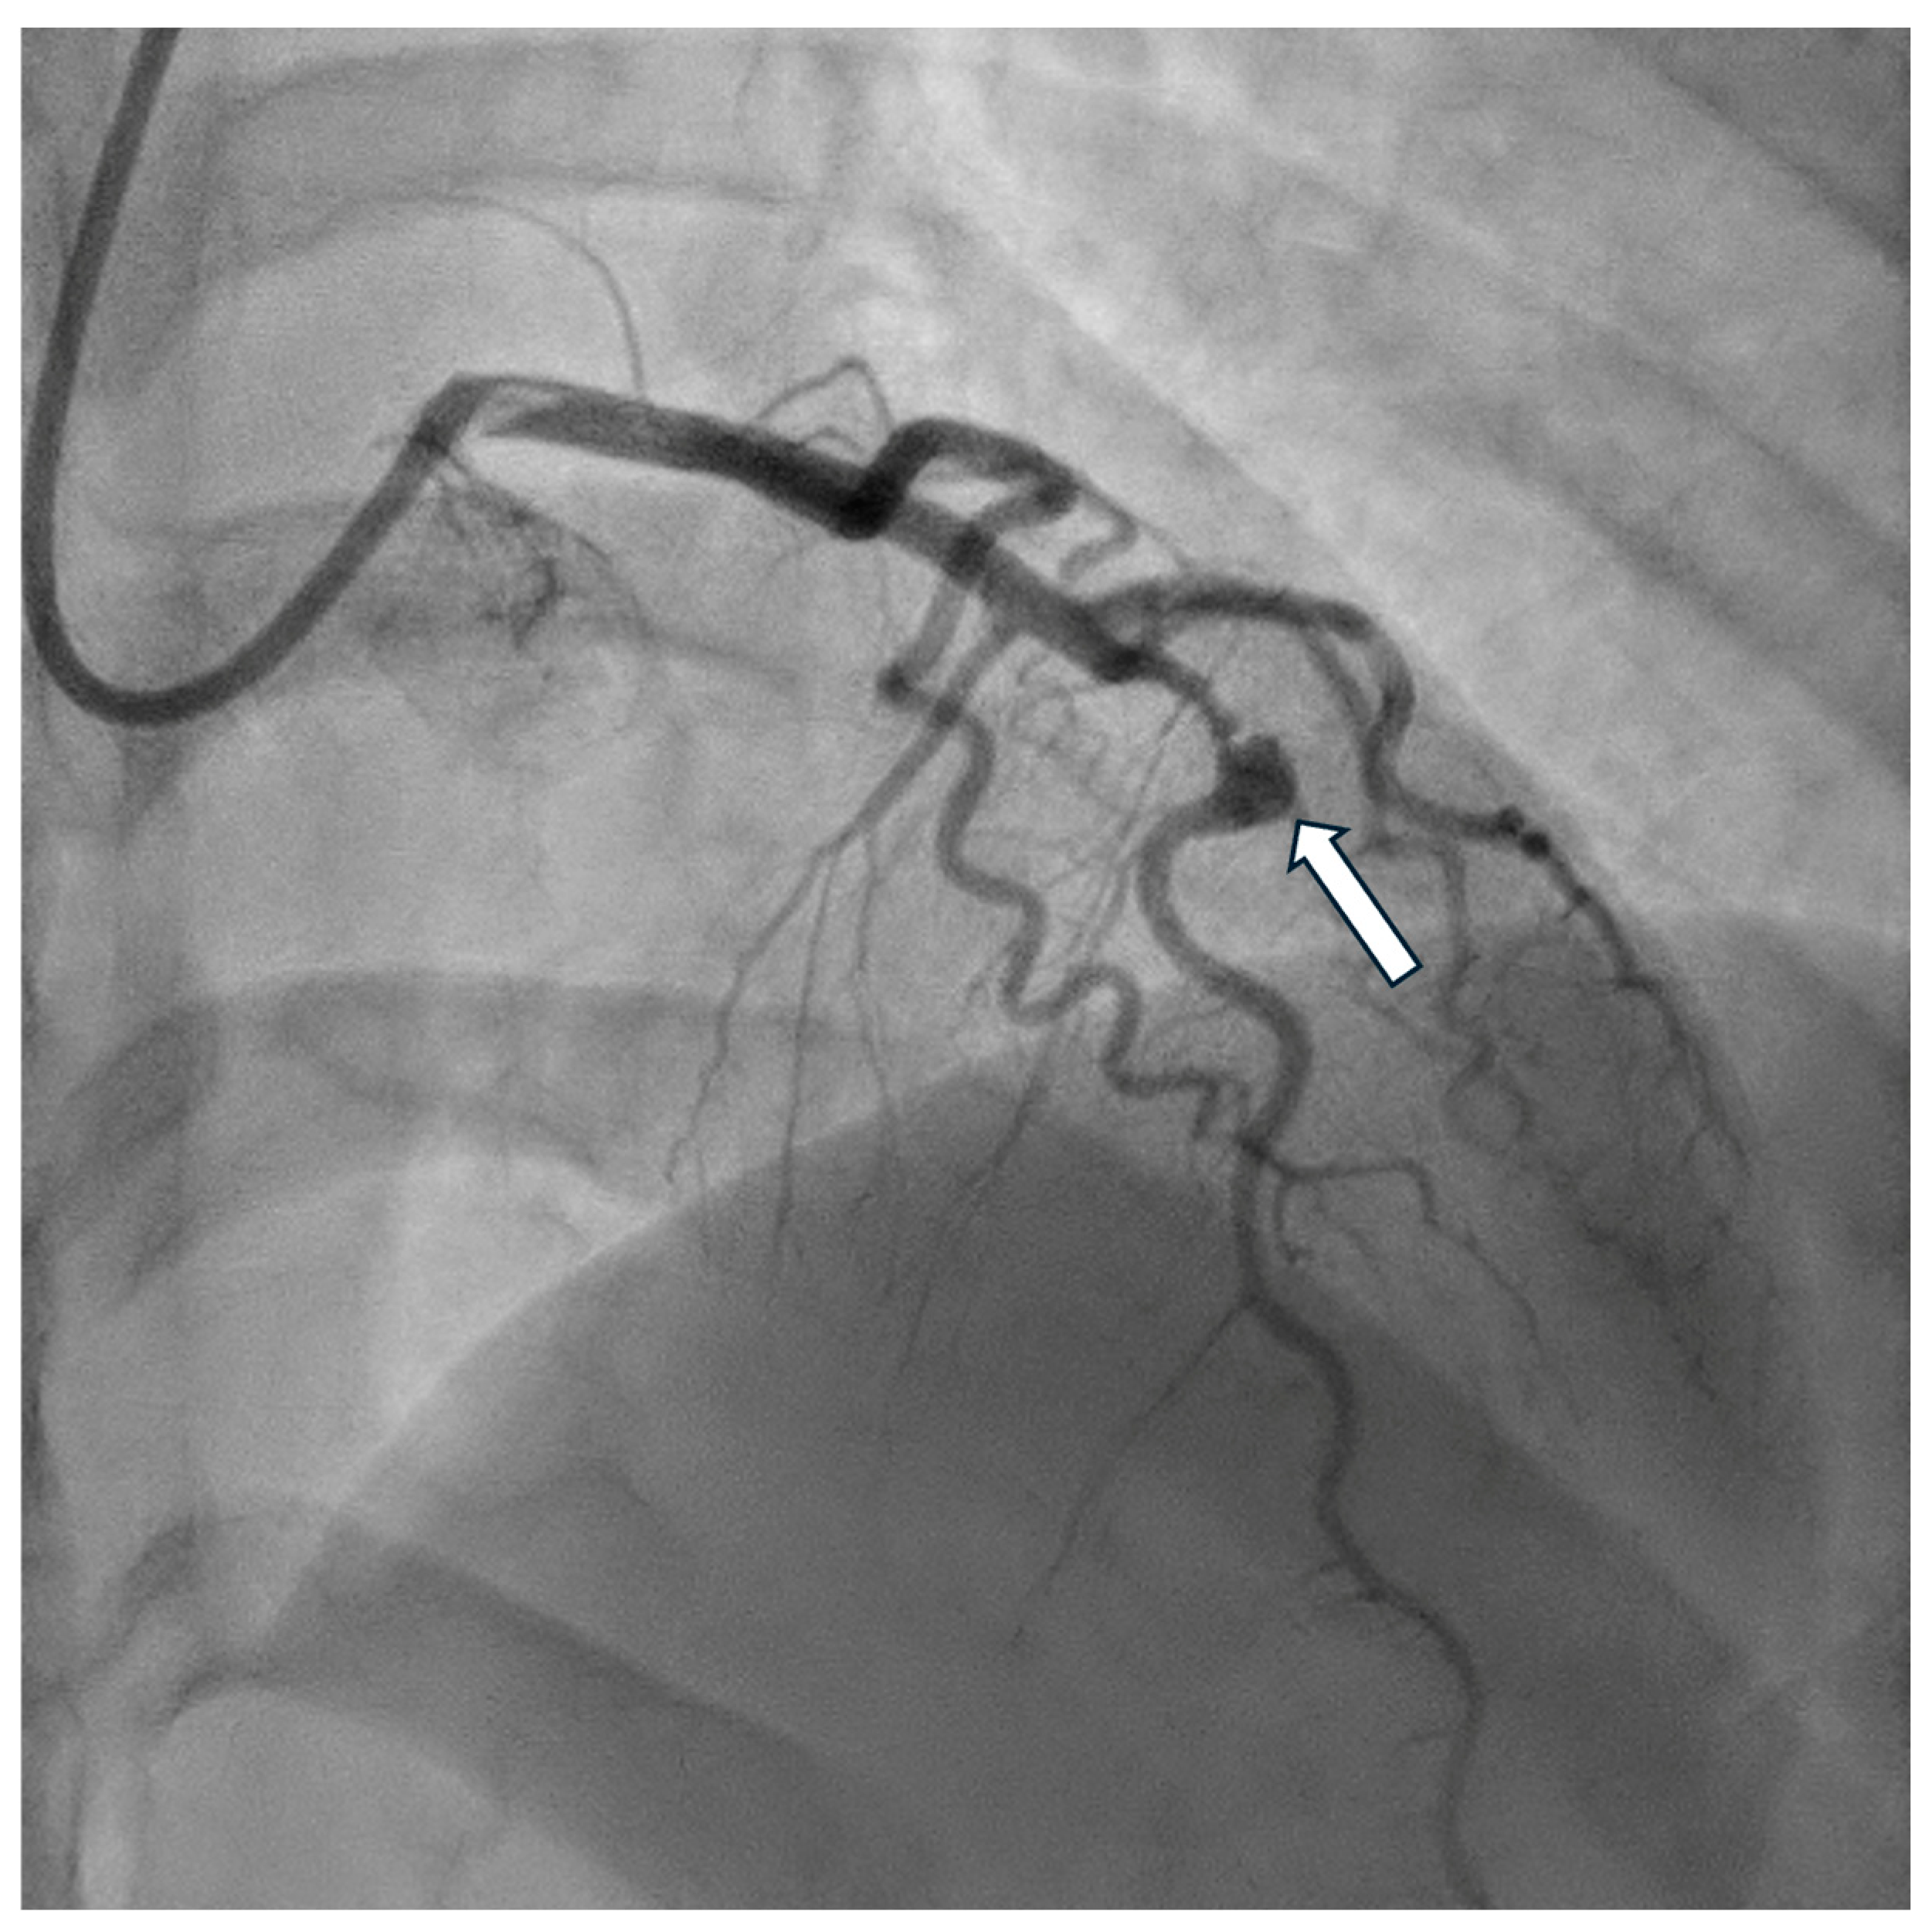

4. Diagnostics

7. Prognosis